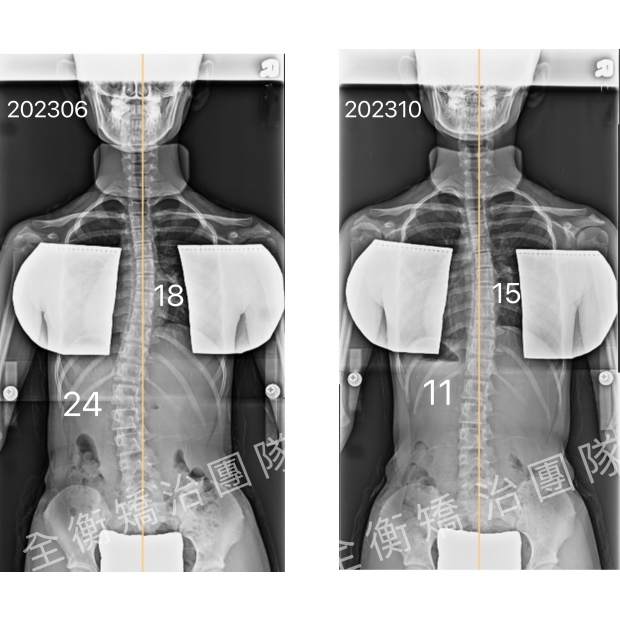

17歲中度側彎男生,積極矯治4個月,度數降低一半17歲中度側彎男生,積極矯治4個月,度數降低一半

17歲,骨齡3,腰彎22度男生,經過4個積極矯治:穿背架+復健運動

度數從22度改善至10度,減少了55% -